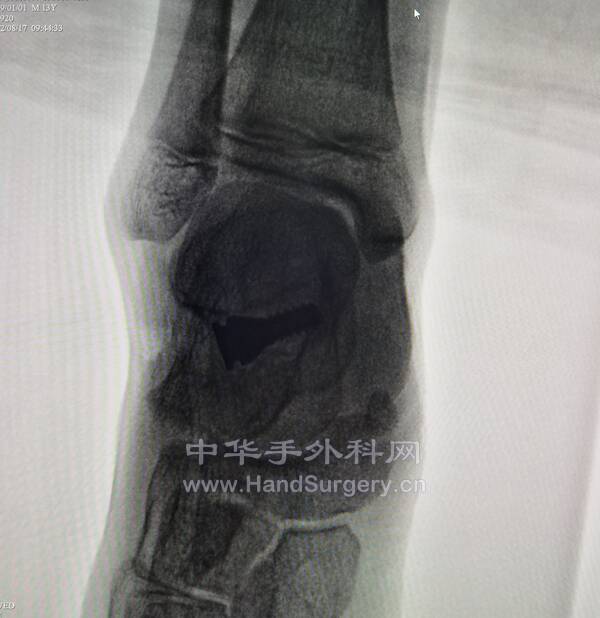

今日得偿所愿,上午跟着老师参观双侧青少年柔韧性扁平足微创扁平足制动器矫正术,双侧副舟骨切除胫后肌腱止点重建术的

13岁男性患者,用的威高扁平足制动器(但大博2代扁平足制动器相对较好)。

副舟骨切除,用直径3.0mm可吸收螺钉固定,与胫后肌腱加固缝合,腱骨缝合,用2.5mm克氏针在舟骨上打孔,放入强生直径3.0mm可吸收铆钉(丝线亦为50%可吸收线),远端与胫后肌腱编织缝合加固!术后6周不能行走。